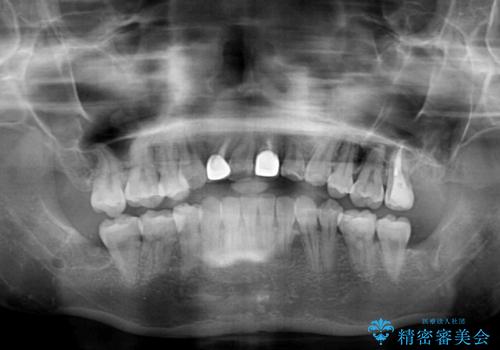

- 奥歯が痛いとのことで来院された患者様です。

上顎親知らず周辺の炎症と、神経組織の失活した歯の炎症による痛みが認められたため、親知らずの抜歯と根管治療を行いました。

根管治療を行った歯はクラウンによる補綴治療が必要となりますが、高校生の頃に行った矯正治療の後戻りも気になるとのことで、補綴治療を行う前に矯正治療を行うこととしました。

後戻りは軽度であり、インビザラインにて歯列を整え、その後にオールセラミッククラウンにて補綴治療を行うこととしました。